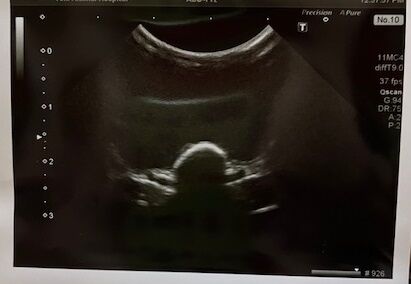

術前検査のレントゲン

特に問題ありません。

※クリックで拡大見れます。